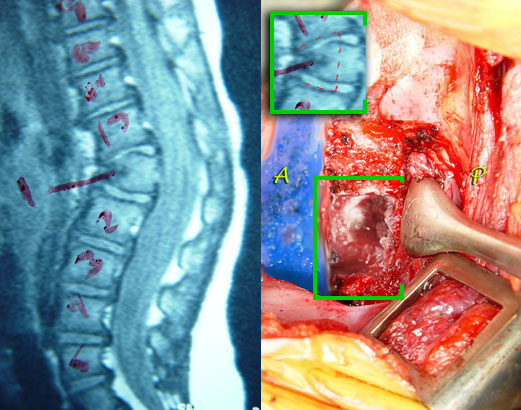

This gibbous is in a toddler. These can go on to angle so severely so as to cause paralysis. In this case we see a deficiency of the entire front of one vertebral body on x-ray. Here, by MRI, we see the x-ray hole as being made of stuff. That stuff is aborted fibrous cartilage tissue. There were x-rays showing this thing getting more angulated. What do you do?

Stop it.

First the disturbed tissue is removed. But that is NOT what causes the process of further curvature. The progression of kyphosis is caused by the intact portions of the growth plates above and below which are unbalanced. After the disturbed tissue is resected, then the above and below hemi-growth plates are removed as well. We restore the normal contour with a transplanted bone secured with hardware. In essence bone will span this new single unit of once three vertebrae.

We see, above, a wire on the back side where small bone slivers are placed to fuse this same segment from the rear. The x-ray shows the contour restored.

The gibbus or sharp kyphosis is gone, but more importantly, the process which produces it is also annulled.